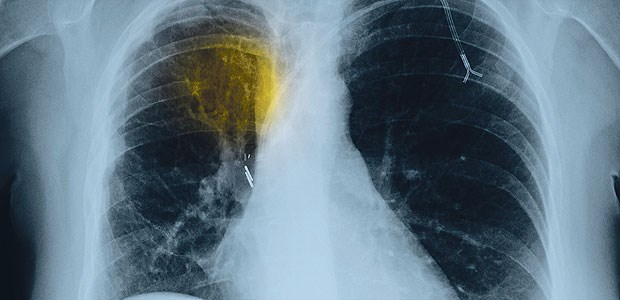

Thorax-Röntgen-Aufnahme einer Patientin mit fortgeschrittenem nichtkleinzelligen Bronchial-Ca.

© Phototake / Mauritius Images

Fortschritte

Lichtblicke in der Lungenkrebs-Therapie